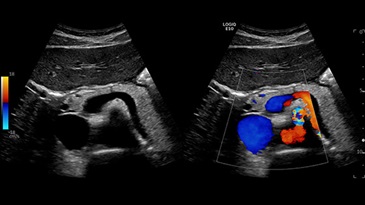

Поджелудочная железа на двойном экране с ЦДК, C1-6-D